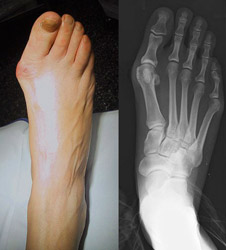

Extended or thickened first ray (or big toe). This common ailment affects a large proportion of the population.

A related condition may affect the fifth ray (little toe) that can be treated in a similar manner.

Often considered hereditary this condition can be caused and agravated through long term use of incorrectly fitted footwear or injury.

Symptoms of bunions familiar to anyone who suffers from them include irritated skin around the bunion, pain when walking, joint redness and pain, and possible shift of the big toe toward the other toes. Blisters and corns may form more easily around the site of the bunion and neighbouring toes.

At Chuckles we evaluate each case individually and have a number of therapeutic techniques such as orthotics that we can choose from as well as building the shoe according to the individual's requirements.